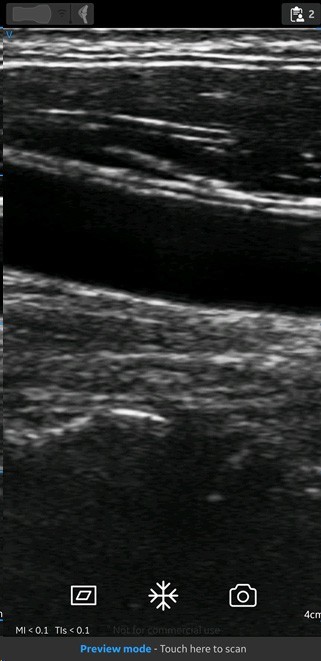

Screen with preview mode

MSK preset with linear